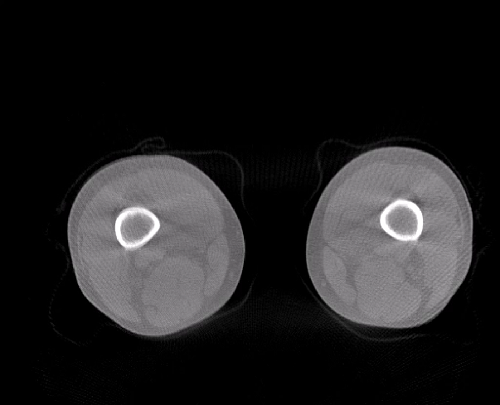

负重位状态下WR-3D断层重建图像